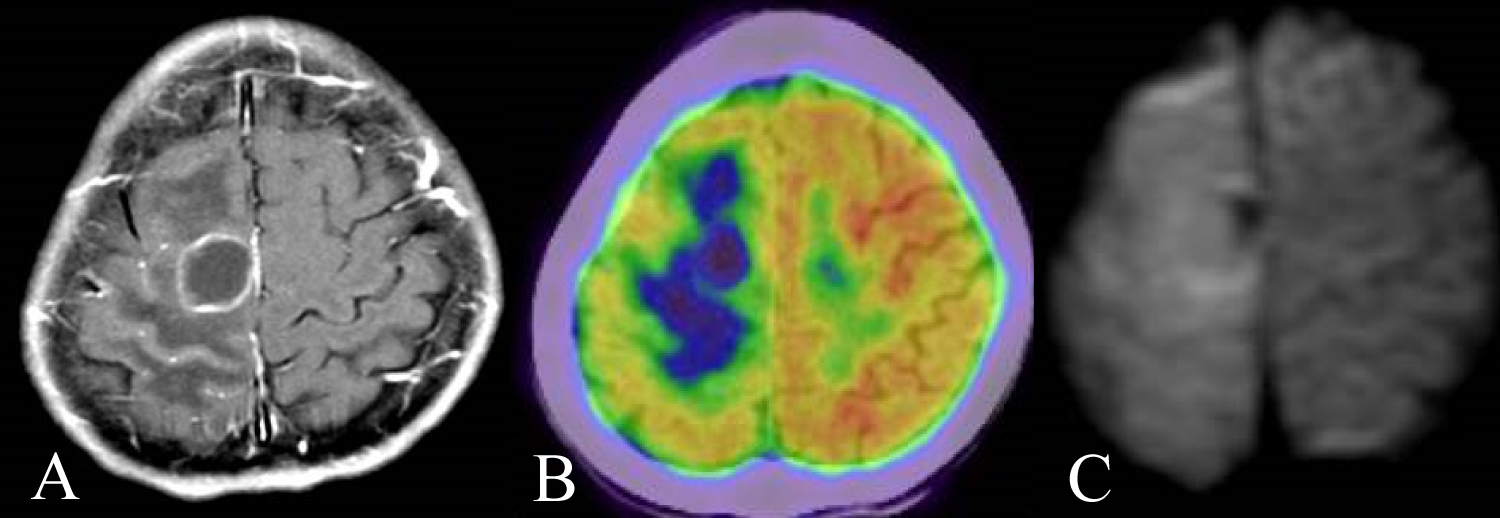

A 42-year-old man presented headache and left hemiparesis of lower limb, and came to our office. We diagnosed his AIDS at 29-year-old and he had been given combined antiretroviral therapy (ART). Contrast MRI showed a ring enhancement lesion in right frontal lobe (Figure 1A). FDG-PET showed central low uptake and moderate uptake at tumor rim (Figure 1B). Meanwhile, diffusion weighted imaging (DWI) showed no clear findings (Figure 1C). At first, we suspected toxoplasmosis and performed stereotactic biopsy. The histopathological findings were diffuse large B cell lymphoma (DLBCL) against our expectations. We performed whole brain radiotherapy as adjuvant therapy. Due to low CD4 positive T cell in number, we could not induce chemotherapy. Although we expected his severe prognosis, he survives at 145 months.

Figure 1: A) A 42-year-old man presented headache and left hemiparesis of lower limb. Contrast MRI showed a ring enhancement lesion in right frontal lobe; B) FDG-PET showed central low uptake and moderate uptake at tumor rim; C) DWI showed only edematous findings. Although we suspected toxoplasmosis at first, the histopathological findings were DLBCL. View Figure 1